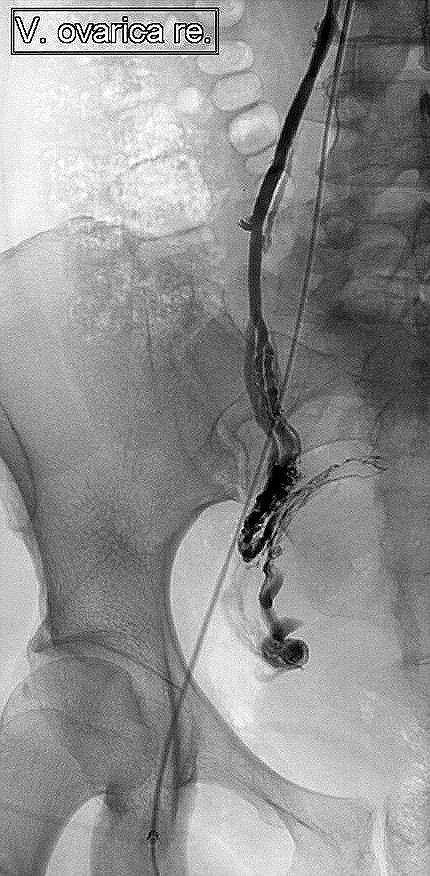

Außerdem müssen als bildgebende Untersuchungen zunächst der Ultraschall der Ovarien und bei sehr hohen Androgenwerten mit Tumorverdacht und unauffälliger Vaginalsonographie ein MRT der NNR erfolgen. Wie im hier berichteten Fall sollte eine selektive Katheteruntersuchung durchgeführt werden, wenn oben genannte bildgebende Verfahren keine Klärung bieten. Dabei wird ein Katheter über die Vena Iliaca und die Vena cava zu den jeweiligen venösen Abflüssen der Nebennieren und der Ovarien geführt, um Hormonserumbestimmungen im Abstromgebiet des jeweiligen Organs selektiv durchzuführen.

Abbildung 1

Abbildung 1: Selektive Stufenkatheterunterschung: Kathetergestützte Kontrastmitteldarstellung des venösen Abstromgebietes des rechten Ovars vor der Entnahme einer selektiven Serumprobe zur Hormonwertbestimmung.